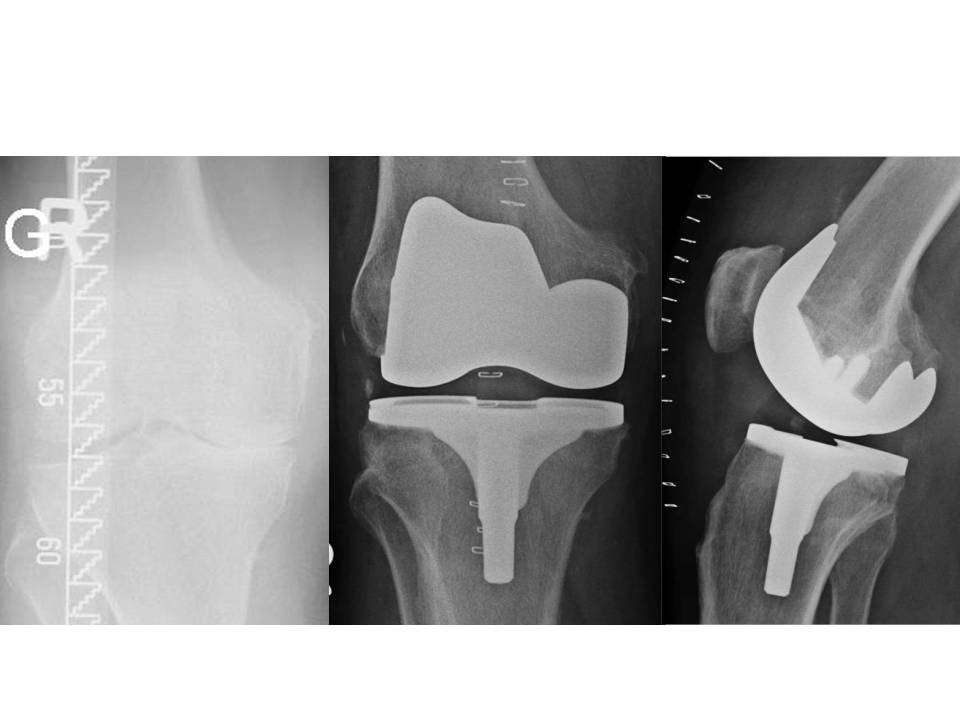

Hamburg, Deutschland) implantiert wurden. Für den Zuschnitt der Femurkondyle und des Tibiaplateaus wurde in der Gruppe mit dem PMI-System das System VisionaireTM (Smith&Nephew, Hamburg, Deutschland) genutzt. Im Zeitraum zwischen Januar 2008 und Dezember 2015 wurden im Hause 15 Patienten mit einer posttraumatischen Kniegelenksarthrose endoprothetisch versorgt. Hiervon waren zwei Patienten prä- und postoperativ auswertbar. Eine 63-jährige Patientin mit posttraumatischer Arthrose nach Tibiakopffraktur (Abb. 1) wurde mittels PMI-System versorgt (Abb. 2). Ein weiterer Patient (72 Jahre alt) wurde mit herkömmlicher Implantation versorgt (Abb. 3). Die Daten der Outcomes wurden mit hauseigenen Daten von 87 Patienten mit herkömmlicher Implantation und 84 Patienten mit PMI-gestützter Implantation verglichen. Das Durchschnittsalter der Patienten lag bei 71 respektive 66 Jahren. Das funktionelle Outcome wurde anhand des Oxford Knee Score und des Bewegungsumfanges beurteilt. Das radiologische Ergebnis wurde über die Veränderung der Knieachse sowie durch Bestimmung des medialen proximalen Tibia- und des distalen lateralen Femurwinkels (MPTA bzw. LDFA) in der Ganzbeinstandaufnahme sowie in der Messung des Slope in der seitlichen Aufnahme des Kniegelenks beurteilt. Es erfolgte die deskriptive Statistik mit Ermittlung von Maximum, Minimum, Mittelwert und Standardabweichung. Die Signifikanzprüfung erfolgte mittels Mann-Whitney-U-Test, wobei ein p-Wert von < 0,05 als signifikant angesehen wurde. Die statistische Auswertung aller Parameter erfolgte mit SPSS (Version 21.0).

Bei der Patientin mit posttraumatischer Gonarthrose, die mittels PMI versorgt wurde betrug der MPTA 89° und der mLDFA ebenfalls 89°. Der Slope lag bei 3°. Die mechanische Lastachse kreuzte das Tibiaplateau 2 mm medial des Fujisawapunktes. Die vorbestehende Valgusgonarthrose konnte somit gut korrigiert werden. Den radiologischen Verlauf zeigen die Abbildungen 1 und 2.